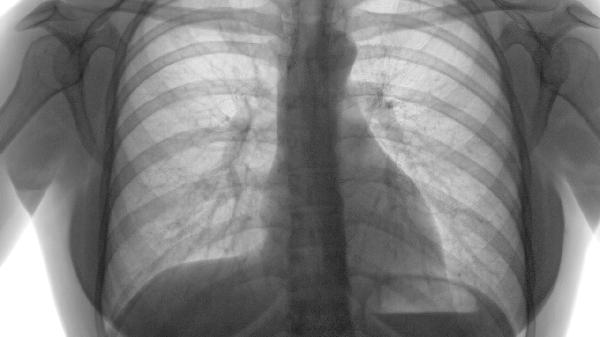

肺气肿可通过药物治疗、氧疗、肺康复训练、手术治疗、生活方式调整等方式治疗。肺气肿通常由长期吸烟、空气污染、遗传因素、职业粉尘接触、反复呼吸道感染等原因引起。

肺减容术适用于上叶显著气肿的患者,可切除无功能肺组织;肺移植适用于终末期病例,需严格评估适应症。术后需加强呼吸道管理。

肺气肿患者日常需保持环境湿度40%-60%,冬季注意保暖。饮食宜高蛋白、高维生素,适量增加深海鱼、核桃等富含ω-3脂肪酸的食物。进行呼吸操训练时,建议采用每分钟8-12次的深慢呼吸节奏。体重指数建议维持在18.5-24之间,肥胖者需减重,消瘦者需营养支持。定期监测肺功能,每年至少进行1次胸部CT检查。出现咳痰增多、气促加重时应及时就医。